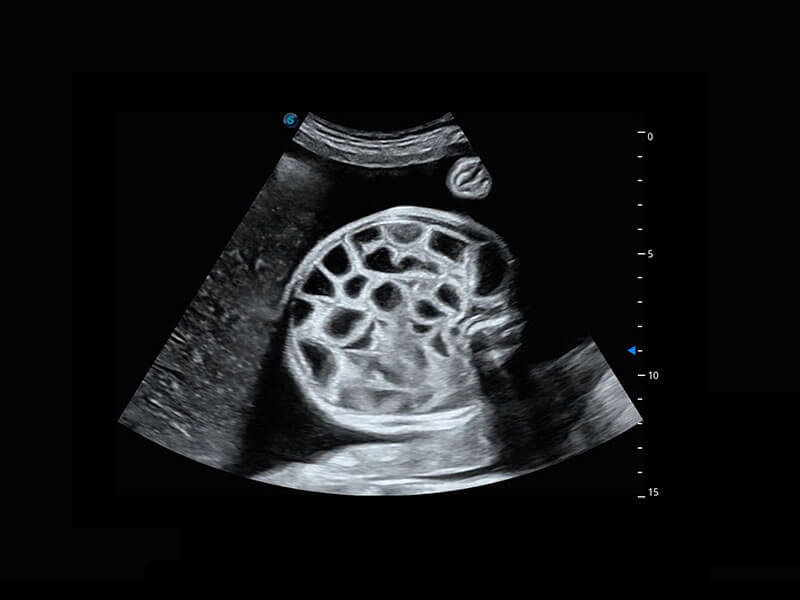

• 胎心容积成像

P60搭载一系列胎儿心脏成像技术,实现精细的胎儿心脏评估。